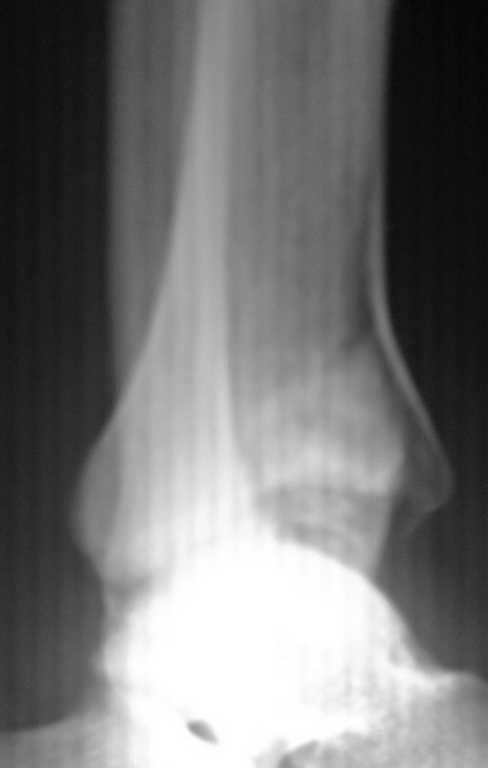

Re: Перелом дистального метаэпифиза ББ кости

послал Димтрий бондарь 27 Август 2008, 22:27

Приветствую ! Что то вторая проекция не прошла :((

Пересылаю